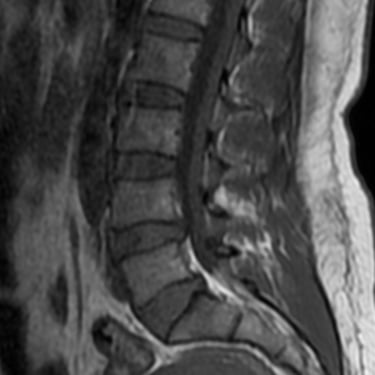

La hernia de disco lumbar se produce cuando el núcleo pulposo del disco intervertebral se desplaza y comprime las raíces nerviosas, generando dolor lumbar, ciática y debilidad en las piernas. El diagnóstico por resonancia magnética (RMN) es el método más preciso para identificar el nivel afectado y el grado de compresión nerviosa. Este estudio permite evaluar la morfología del disco, el canal vertebral y las estructuras adyacentes, orientando el tratamiento médico o quirúrgico. La detección temprana mediante RMN es fundamental para prevenir daño neurológico y planificar una intervención segura y efectiva en caso necesario.